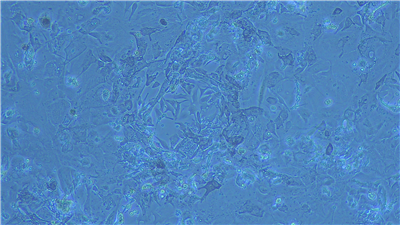

所谓原代分离,就是将组织或细胞从原始样本中分离出来,并单独进行培养和研究。相比于传统的细胞培养技术,原代分离技术能够更好地保持细胞的原始状态,使其能在体外环境下维持生存并进行正常代谢和生长。这为研究细胞的生物学特性、功能和调控机制提供了重要的手段。

原代分离的过程并不简单,需要经过多个步骤。首先需要选择适合的组织或细胞来源,并对其进行消化、分散和筛选等处理,以获得单个细胞或小团块。然后将这些细胞种植在含有营养物质和生长因子的培养基中,待其生长成为一个稳定的细胞系后,再进行相关实验。